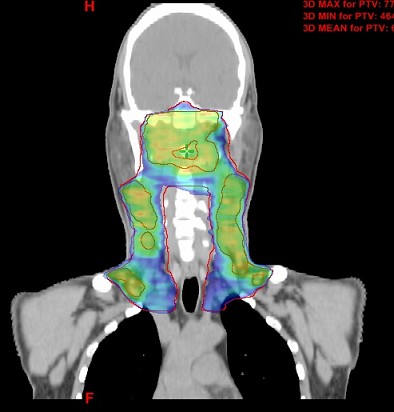

图3 医用直线加速器治疗头颈肿瘤病例